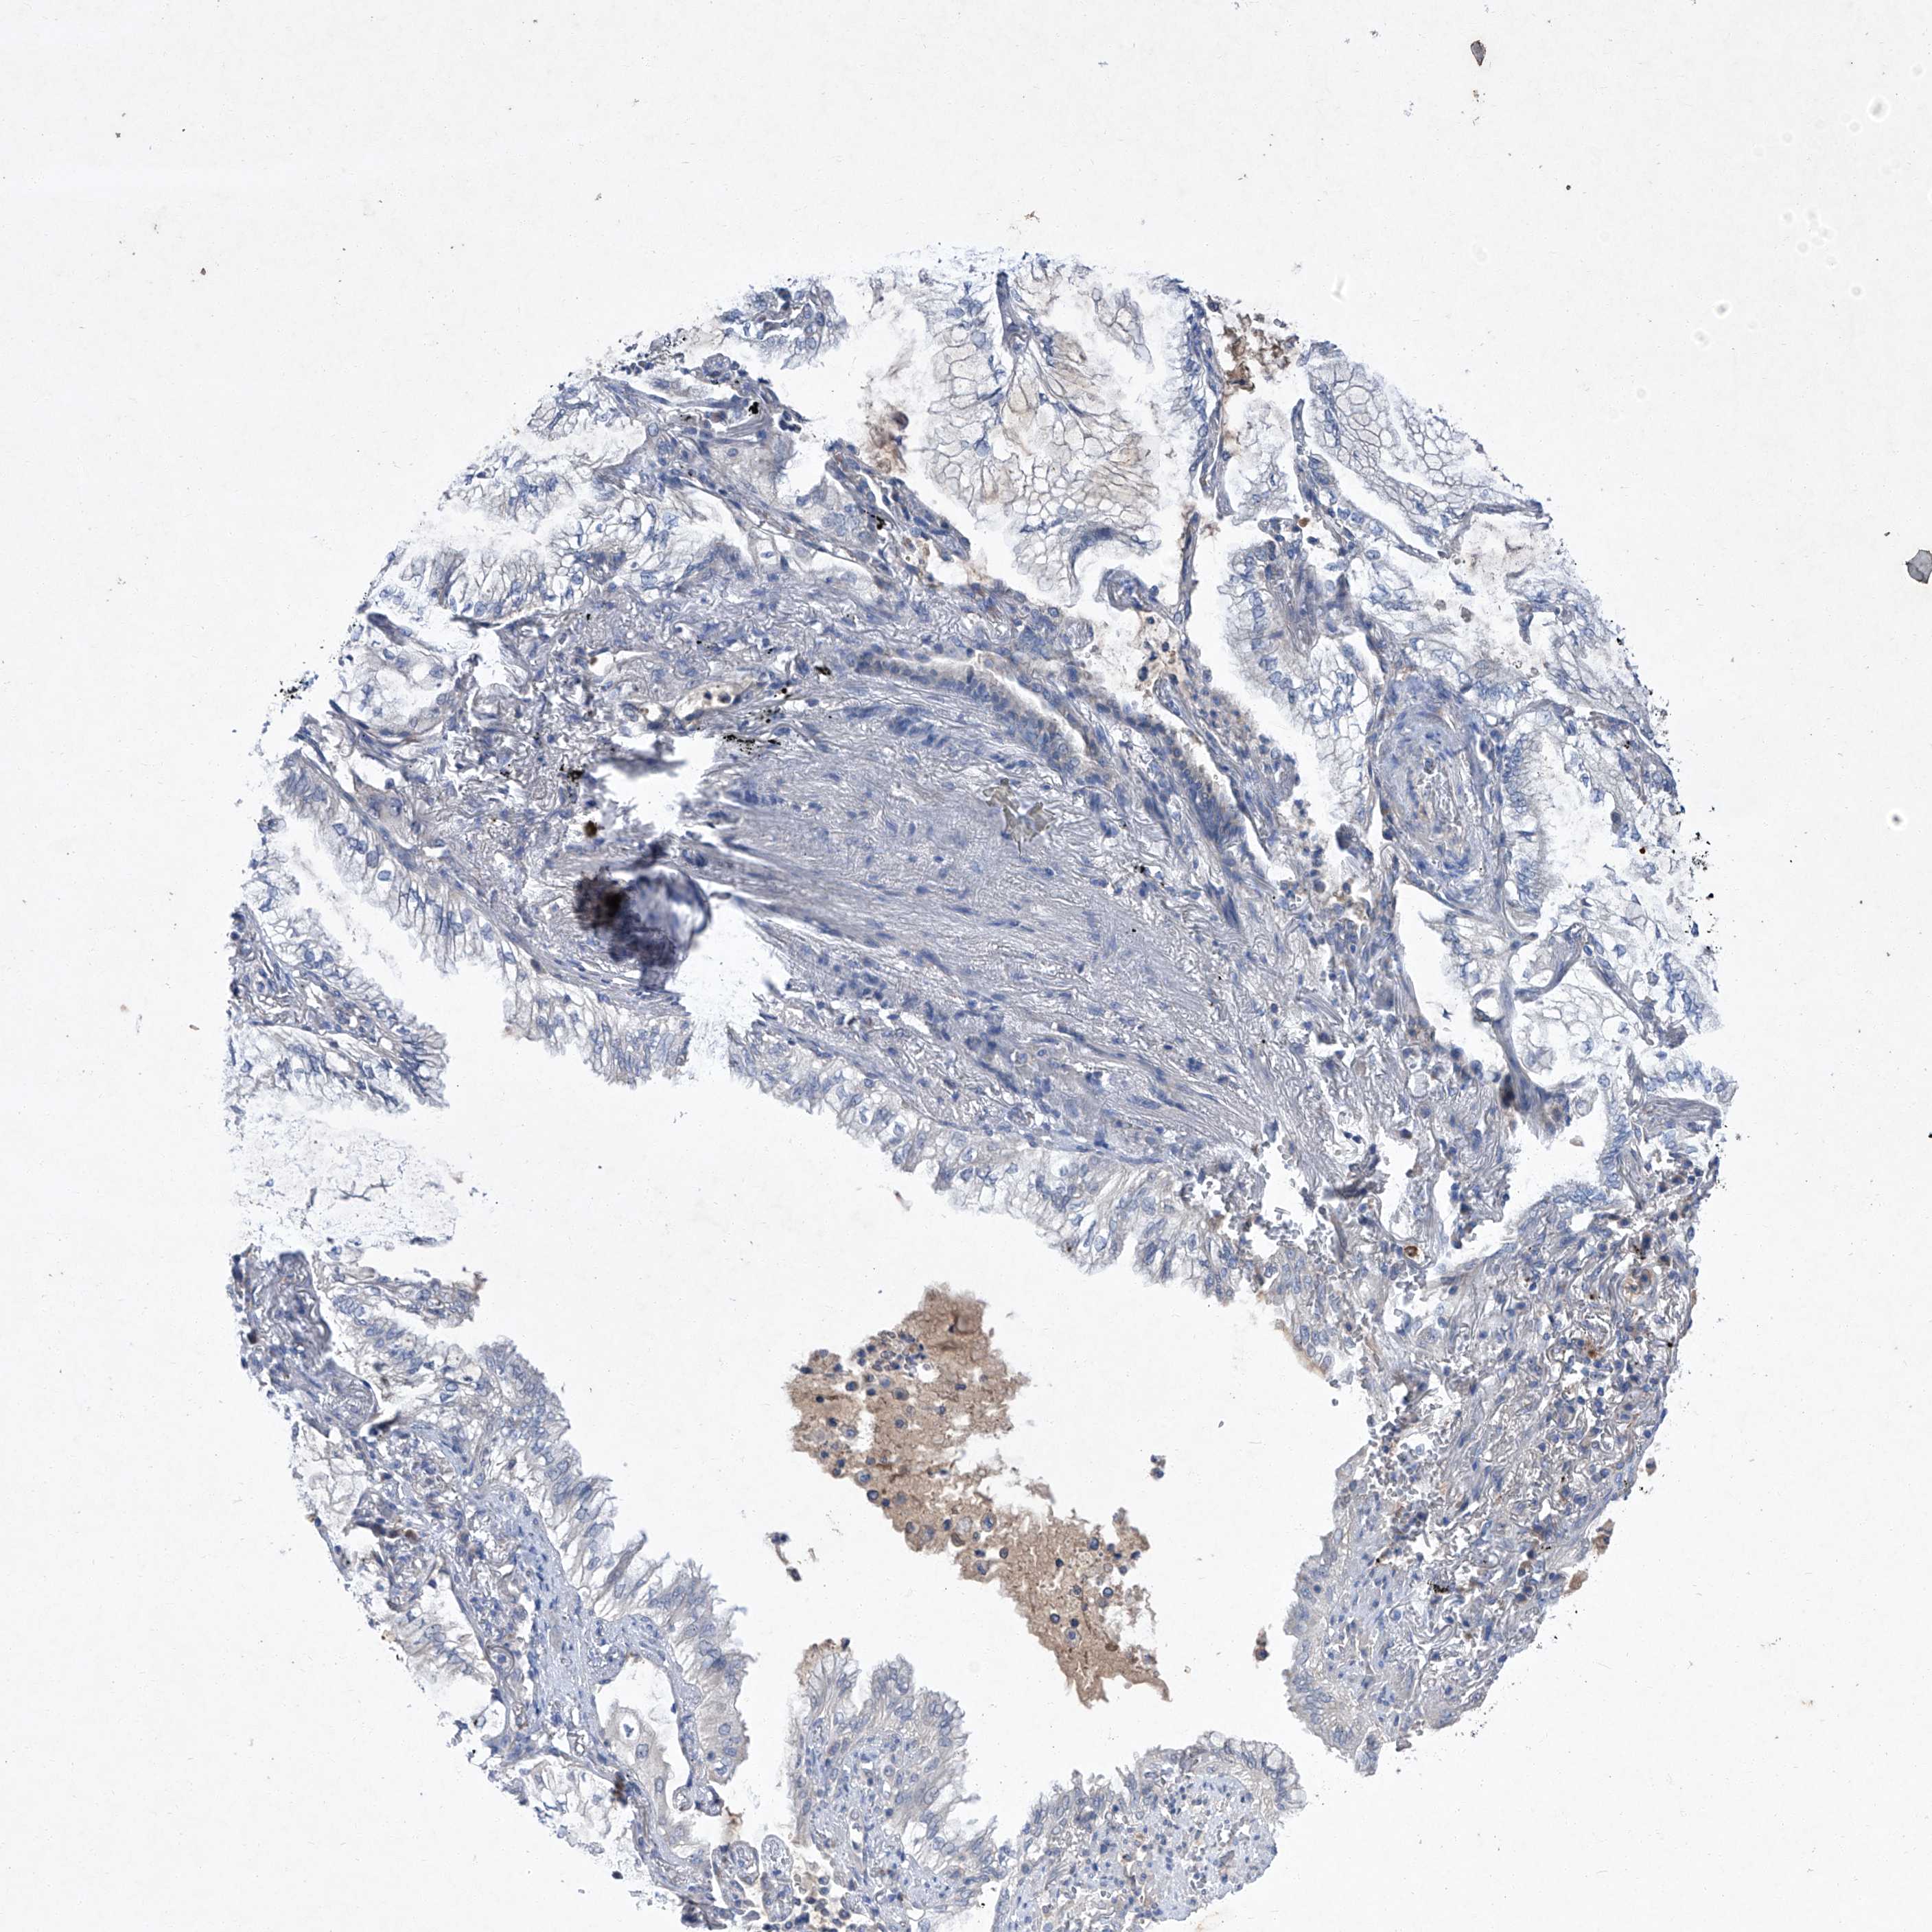

LUNG ADENOCARCINOMA (VALIDATION) - Interactive survival scatter ploti

The Survival Scatter plot shows the clinical status (i.e. dead or alive) for all individuals in the patient cohort, based on the same data that underlies the corresponding Kaplan-Meier plots. Patients that are alive at last time for follow-up are shown in blue and patients who have died during the study are shown in red.

The x-axis shows the expression levels (FPKM) of the investigated gene in the tumor tissue at the time of diagnosis. The y-axis shows the follow-up time after diagnosis (years). Both axes are complimented with kernel density curves demonstrating the data density over the axes. The top density plot shows the expression levels (FPKM) distribution among dead (red) and alive patients (blue). The right density plot shows the data density of the survived years of dead patients with high and low expression levels respectively, stratified using the cutoff indicated by the vertical dashed line through the Survival Scatter plot. This cutoff is automatically defined based on the FPKM cutoff that minimizes the p-score. The cutoff can be changed by dragging the vertical line or by entering a cutoff value in the square labeled "Current cut-off".

Under the Survival Scatter plot the p-score landscape (black curve; left axis) is shown together with dead median separation (red curve; right axis). Dead median separation is the difference in median mRNA expression between patients who have died with high and low expression, respectively. It is calculated as follows: median FPKM expression of dead patients with high expression - median FPKM expression of dead patients with low expression. This is intended to aid the user in visually exploring custom cutoffs and the associated p-scores and dead median separation.

Individual patient data is displayed and can be filtered by clicking on one or more of the category buttons on the top of the page. Categories describing expression level and patient information include: high, low, alive, dead, female, male and tumor stages. The scale of the x-axis can be toggled between linear and log-scale by clicking on the "x log" button. Mouse-over function shows TCGA ID, patient information and mRNA expression (FPKM) for each patient.

& Survival analysisi

Kaplan-Meier plots summarize results from analysis of correlation between mRNA expression level and patient survival. Patients were divided based on level of expression into one of the two groups "low" (under cut off) or "high" (over cut off). X-axis shows time for survival (years) and y-axis shows the probability of survival, where 1.0 corresponds to 100 percent.

SBK2 is not prognostic in Lung Adenocarcinoma (validation)